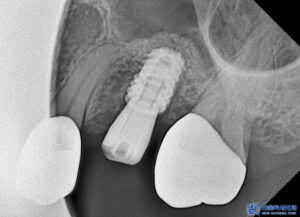

이후 임플란트가 뼈와

잘 결합된 것이 확인되어,

자연치와 조화를 이루는

최종 보철물을 함께

제작·장착하였습니다.

임플란트의 치유 기간이 충분히 지난 뒤,

보철 작업을 진행했습니다.

정밀한 교합과 잇몸 라인을 구현하기 위해

맞춤형 지대주를 제작하고,

이에 맞는 보철물을 장착하였습니다.